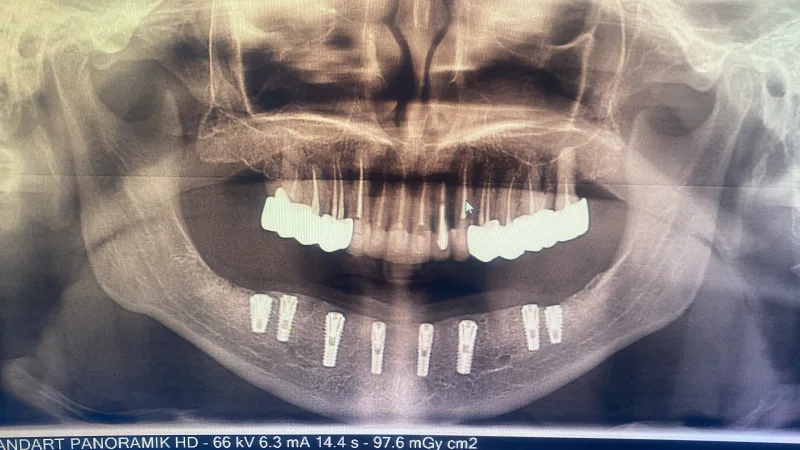

Próteses e implantes de dentes